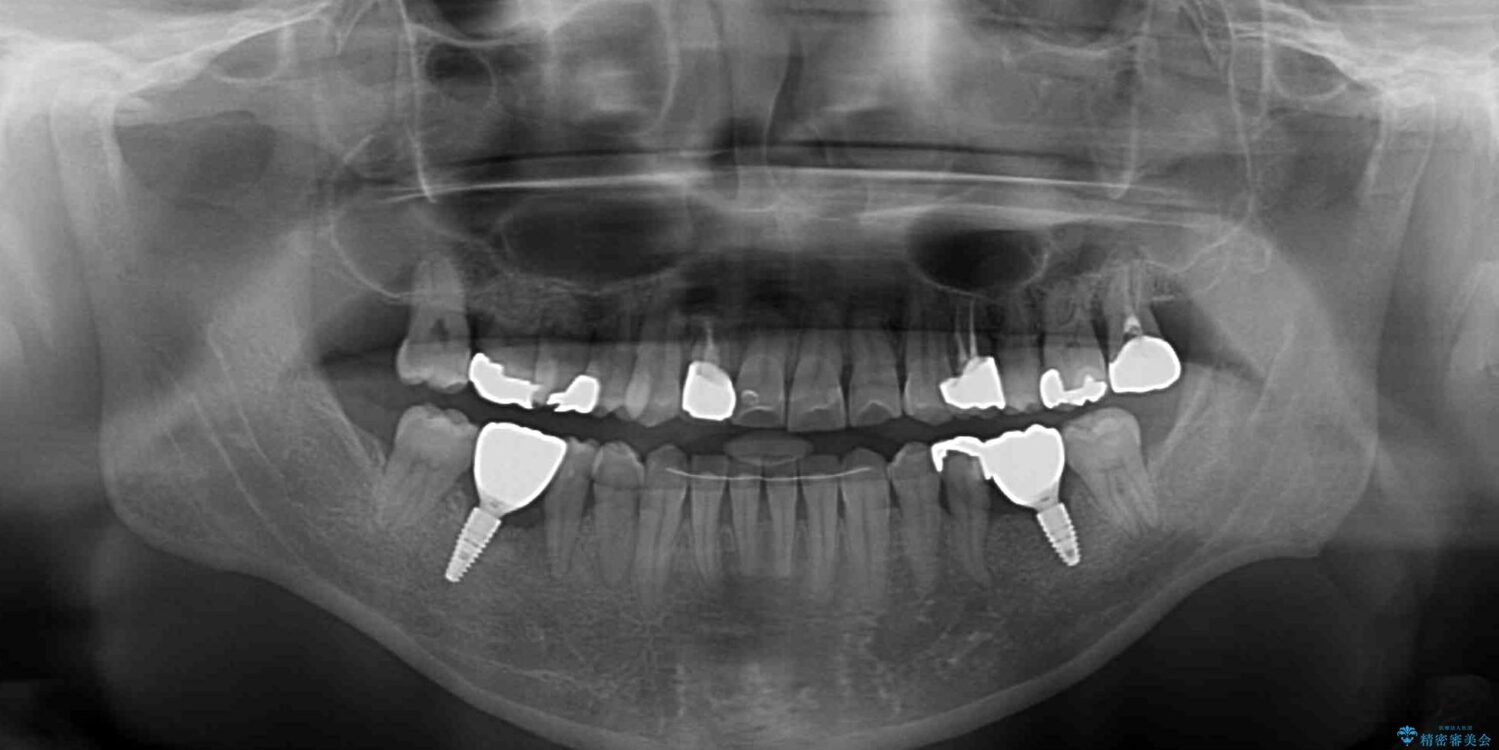

左右下顎の大臼歯は、ともに歯根が破折しており、抜歯が必要な状態でした。

放置したことで炎症による骨吸収が顕著であるため、骨造成を併用してインプラント埋入を行うこととしました。

咬み合わせは受け口傾向であり、上顎前歯の叢生が顕著であったことから、第1小臼歯抜歯による矯正治療も検討しましたが、下顎大臼歯を左右ともに抜歯するため、非抜歯による矯正治療を行うこととしました。

矯正治療でインプラント埋入を行い、矯正治療後に気になる前歯と合わせてオールセラミッククラウンによる補綴治療を行うこととしました。

治療前

• 割れてしまった奥歯とデコボコの前歯 矯正治療とインプラント治療 治療前画像